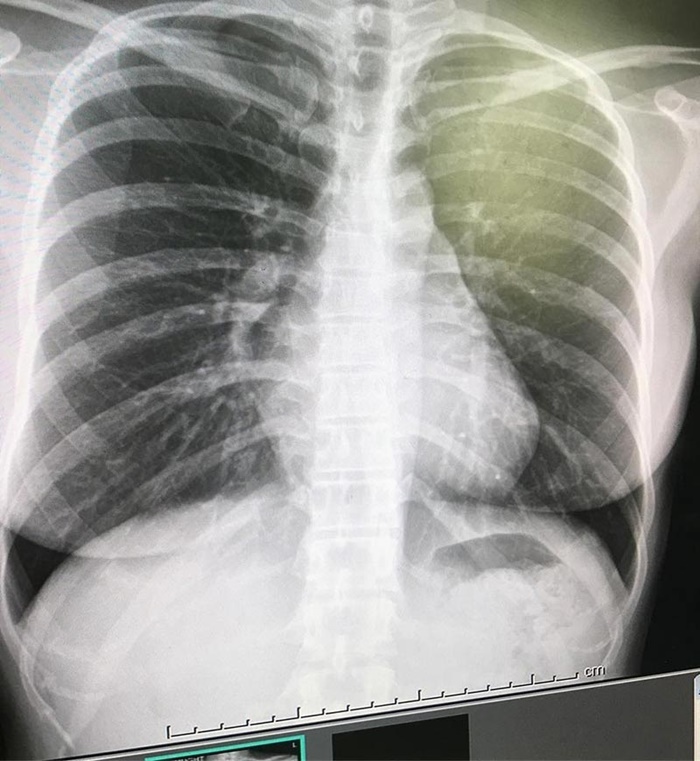

ทำเอาแฟนคลับเป็นห่วงหนักมาก หลังสาวอารมณ์ดี หนูเล็ก ภัทรวดี หรือ หนูเล็ก

ก่อนบ่าย ได้โพสต์ภาพเอกซเรย์ปอดแหว่ง โดยระบุว่าสาเหตุเกิดจากไวรัสลงปอด

แต่ไม่ยอมกินยา ทำให้ภูมิคุ้มกันต้องต่อสู้กับไวรัสเอง ล่าสุด (7 พฤษภาคม

หนูเล็ก : เรื่องนี้จะมาขอโทษพ่อแม่พี่น้องค่ะ คือเรื่องของเรื่อง หนูไม่ชอบกินยาเลย เวลาเราไม่สบายเราจะไม่ชอบกินยาเลย แล้วรู้สึกว่าภูมิคุ้มกันเราดี พอเราไม่สบาย เราก็ไปเอกซเรย์ หมอก็บอกว่า ที่มันหายไปนั่นแหละคือปอดติดเชื้อ เราก็ตกใจ แล้วหมอเค้ารีบก็พูดไม่ค่อยเยอะ หนูเลยเข้าใจเองว่าที่หมอชี้คือปอด ปรากฏว่าเป็นหัวใจค่ะที่หมอชี้ แล้วคือปอดมันอยู่ข้างหัวใจ มันจะเป็นรอยสีขาว ๆ ซึ่งนั่นคือติดเชื้อ ซึ่งหนูต้องกราบขอโทษด้วยค่ะที่ทำให้เข้าใจผิด ที่อยากเตือนคือ เวลาไม่สบายอย่าคิดว่าภูมิคุ้มกันของตัวเองดี ต้องไปหาหมอกินยานะคะ สรุปหนูเป็นปอดติดเชื้อค่ะ ต้องกินยาต่อเนื่องหลาย ๆ เดือนค่ะ